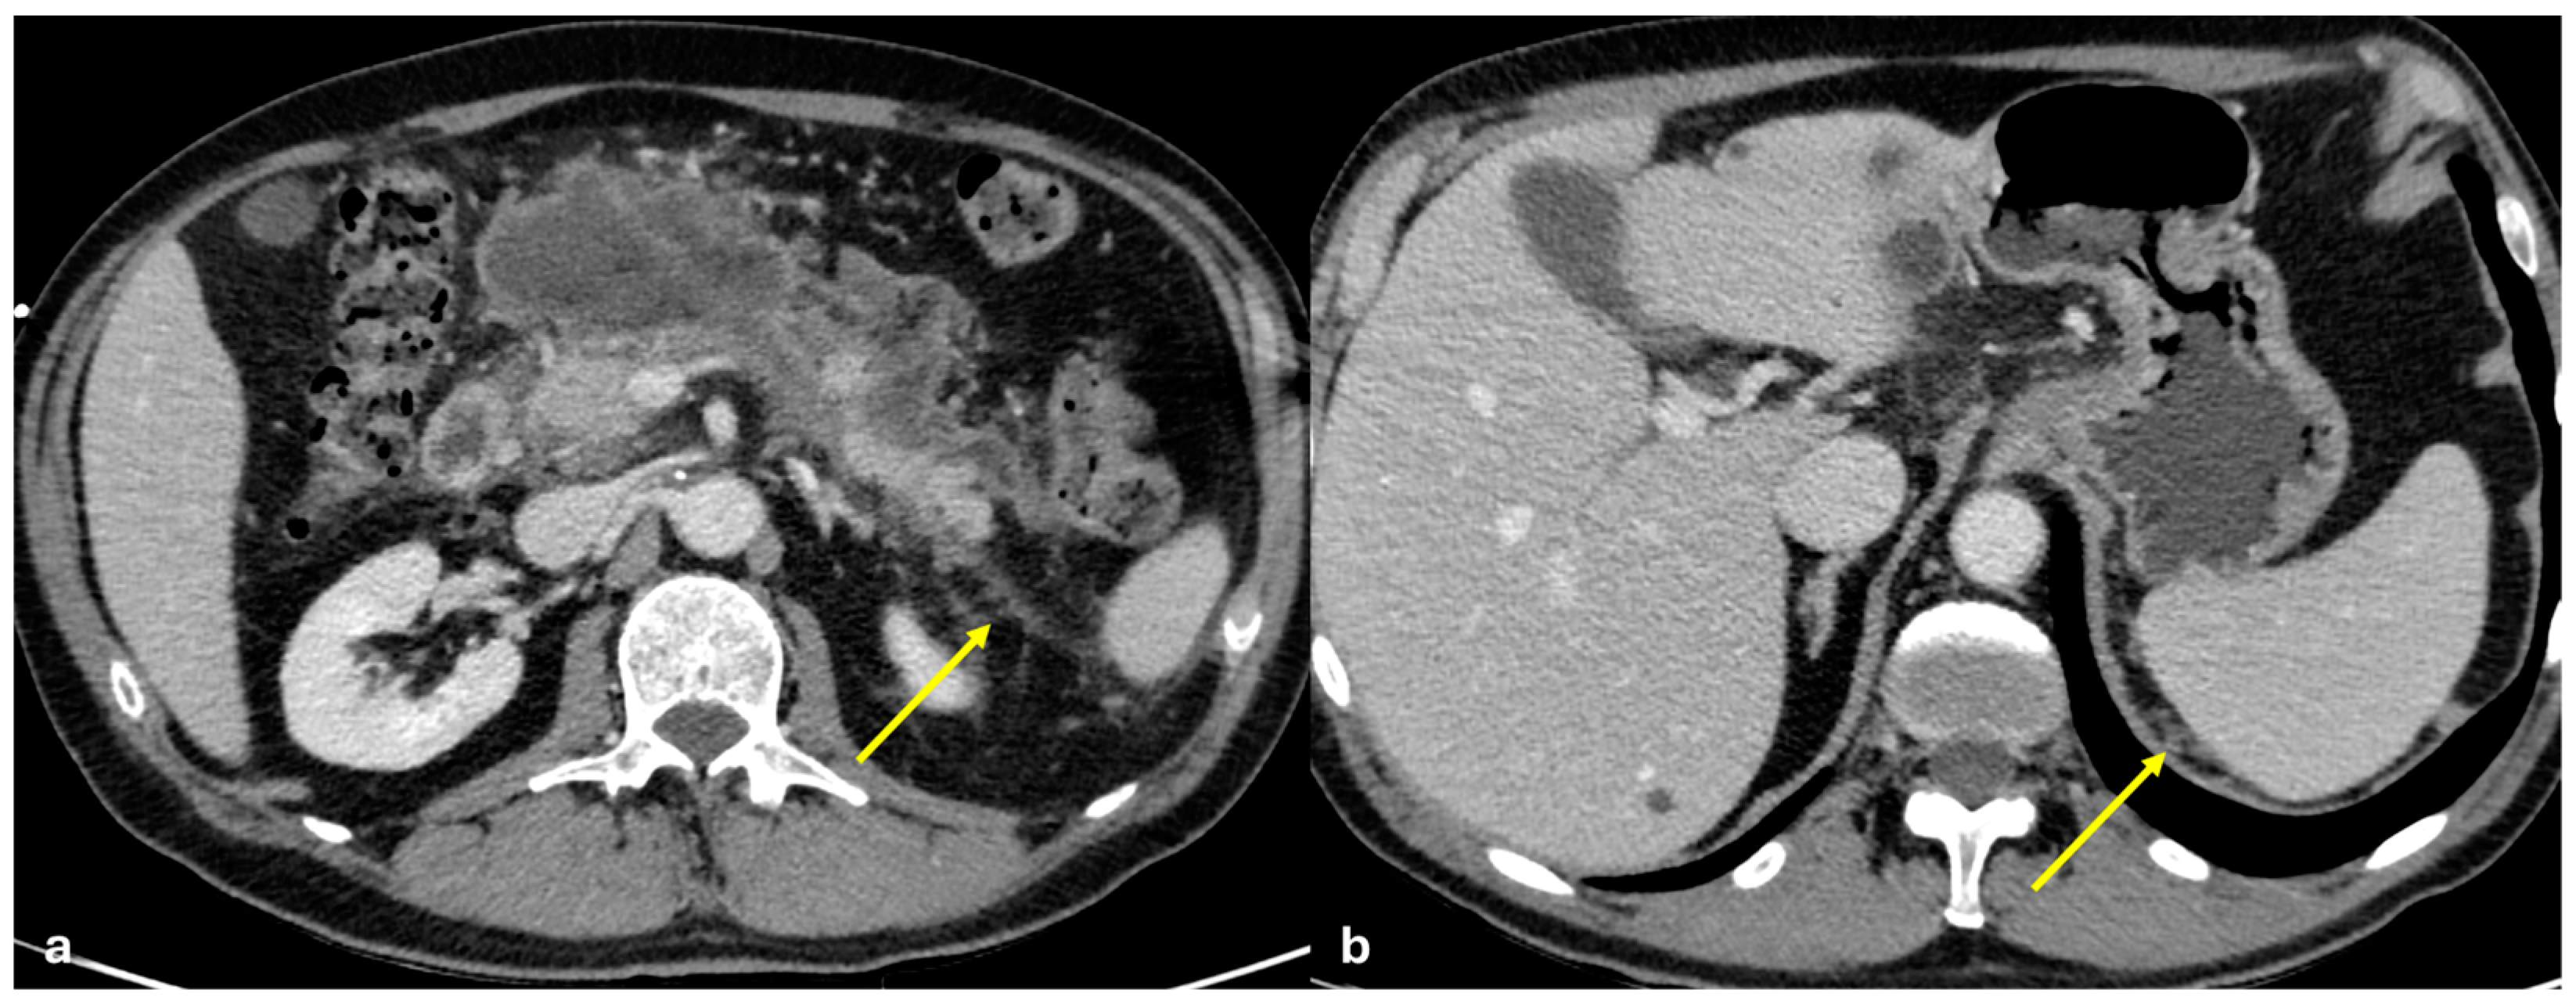

3.3.3. Mesenteric Panniculitis

3.3.4. Subperitoneal Spread of Necrotizing Pancreatitis